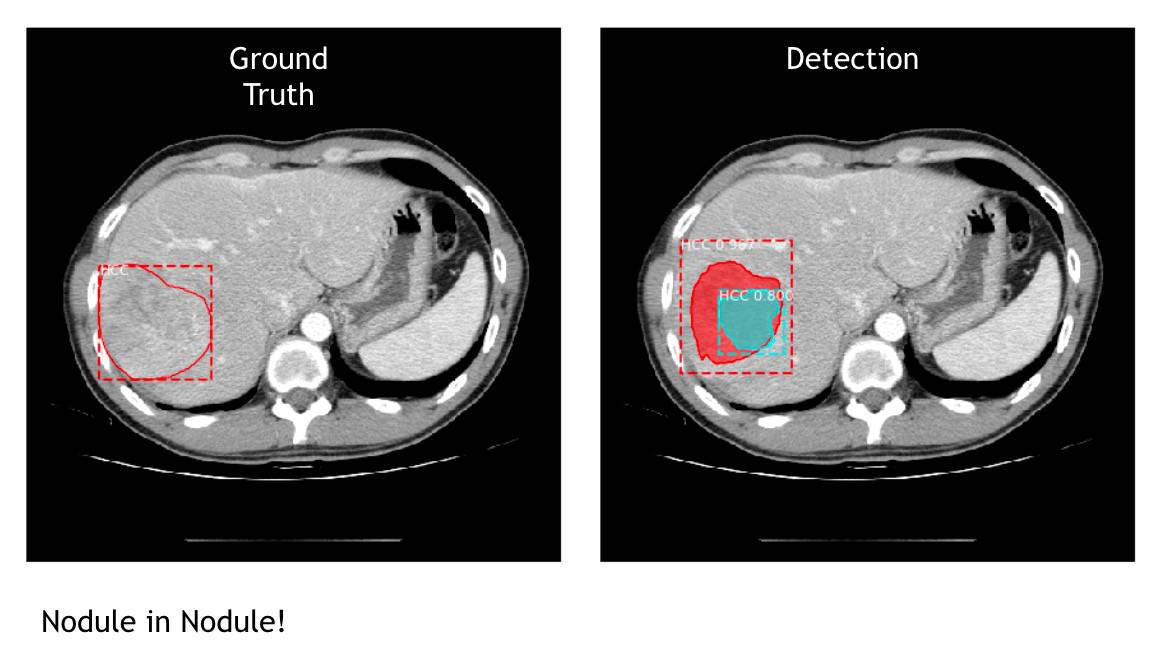

不仅 AI 可以找出肿瘤位置、框出边缘,甚至还出现惊喜,游家鑫指出有两个很特别的状况,一个是他们没有教机器 nodule in nodule 肿瘤中还有一个肿瘤这种低机率低的情况,但它自己找出来了,当初研究人员看到机器标这张图,还以为机器出错,就拿去请教医生,才知道原来这就是 nodule in nodule 。另一个就是有一张素材里有一个“人为标错”的状况,因为有时医生真的太疲累而画错,但机器却自己找出正确的肿瘤位置。

图|这张图就是 nodule in nodule ,他们没有教机器这个状况,但机器自己发现了,不过也值得注意的是,对于第二颗肿瘤机器下判断的自信程度是 HCC 0.8 ,对比一般机器的自信通常都会超过 0.9 来说,它是稍微没有自信,但还是识别出来了。(图片来源:CMUH人工智能医学诊断中心)